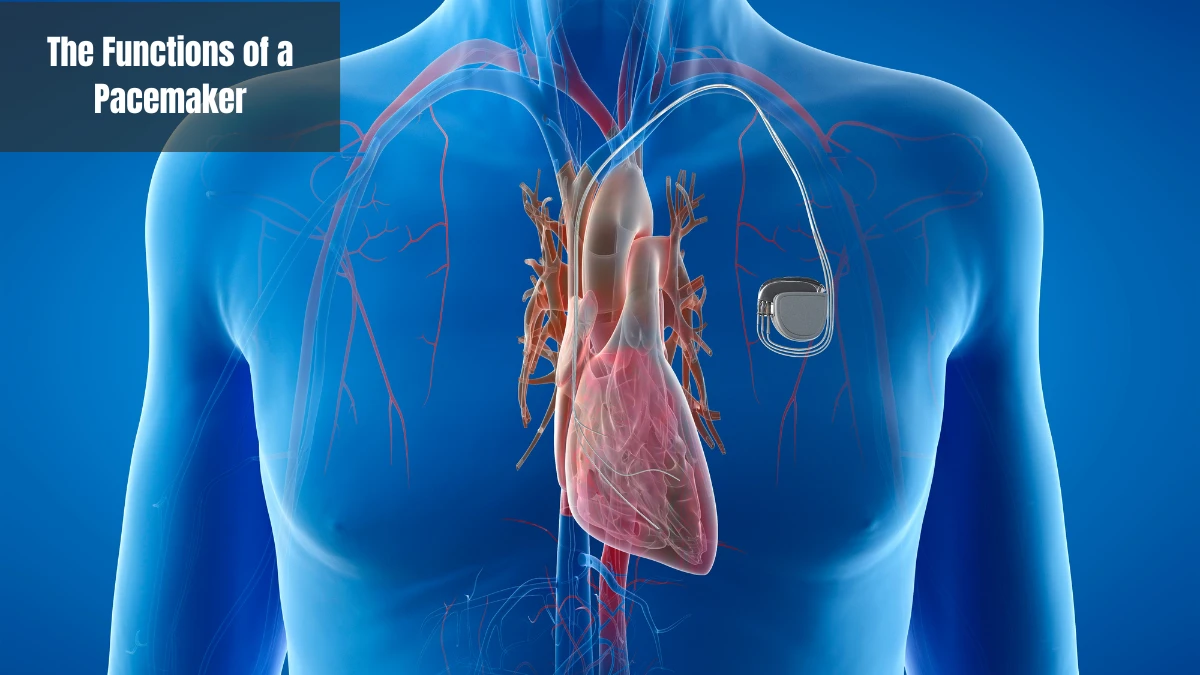

The Functions of a Pacemaker

The pacemaker has several functions, including detecting abnormalities, sending electrical signals, maintaining a normal heart rate, and monitoring the patient's condition. Here are some functions in detail:

Detecting abnormalities

One of the main functions of a pacemaker is to detect abnormalities in the heart rhythm. The implanted device continuously monitors the heartbeat and detects if the heart rhythm is abnormal, faster, slower, or irregular.

Sending electrical signals

The function of sending electrical signals is to stimulate the heart muscles that are detected as abnormal. Electrical impulses to the heart cause contractions and keep the heart rate at a normal frequency. Don't worry, the electrical signals sent do not cause pain.

Maintaining a normal heart rate

An abnormal heart rhythm is very risky for safety. A pacemaker can help the heart beat at a normal speed again. The heart rate frequency will be adjusted based on the body's activity needs.

Monitoring the patient's condition

In addition to functions that can be directly felt by the body, pacemakers also have functions for medical personnel in monitoring the patient's condition. Through the telemetry system, every heartbeat of the patient can be accessed and monitored directly by medical personnel.